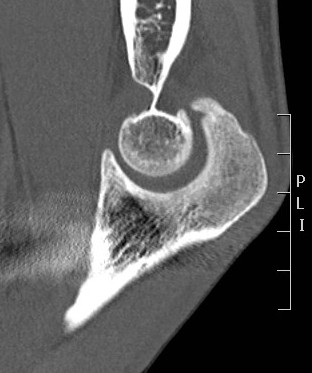

CT

Define olecranon and coranoid process osteophytes

Identification loose bodies

Osteophyte of the olecranon likely impinging in extension